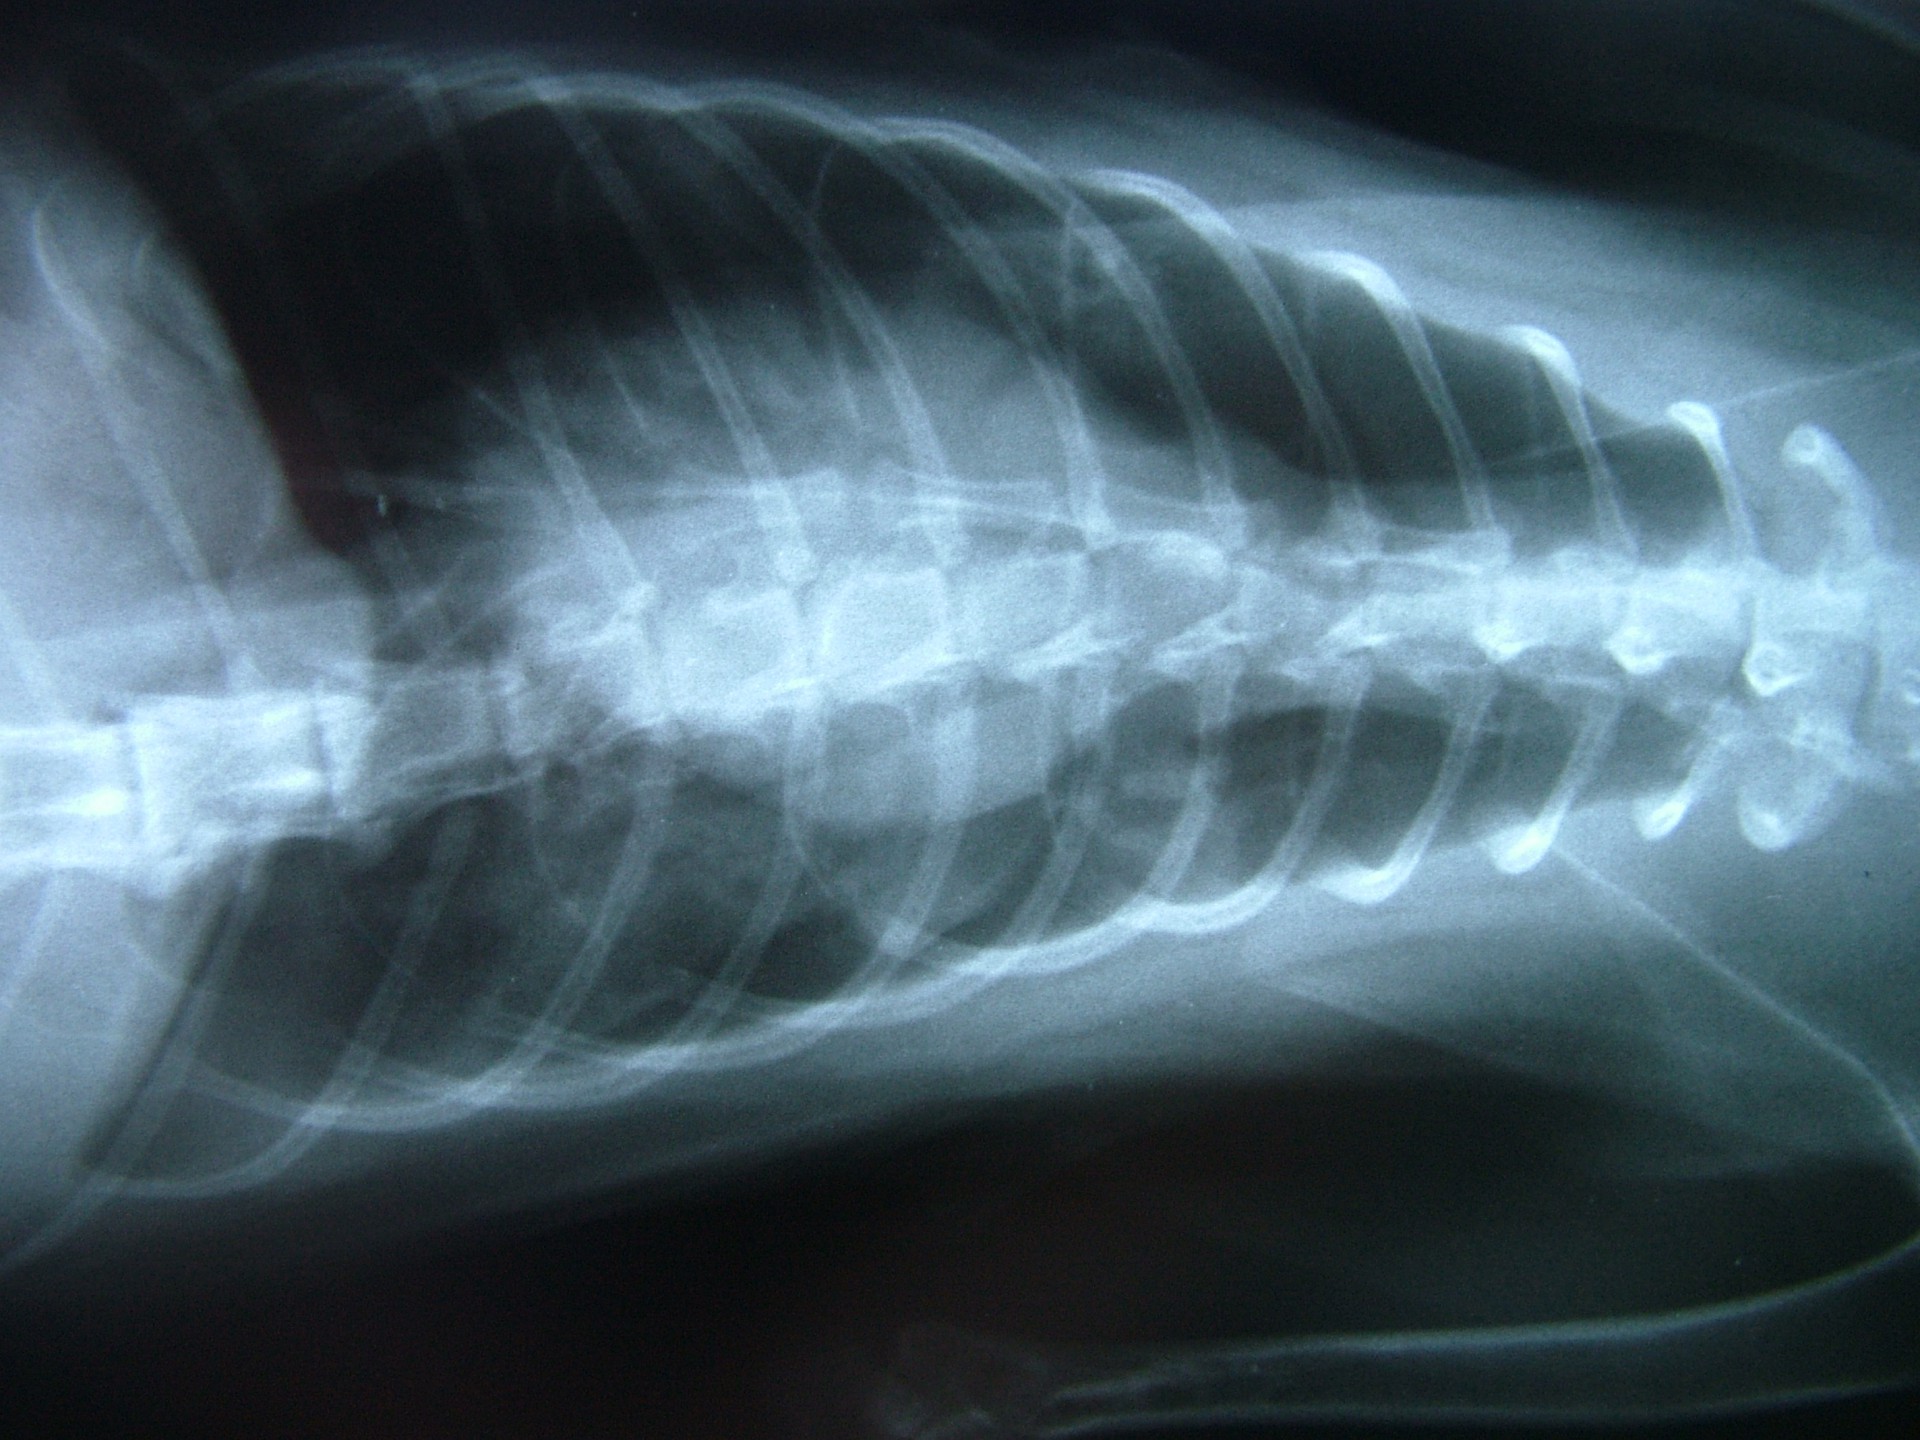

A rekeszizom veleszületett vagy szerzett sérülése, folytonosság hiánya következtében a hasüregi szervek a mellkasba nyomulnak, és összenyomják a tüdőt. Ennek következtében a tüdő nem képes a mellkas mozgását követni és elsősorban a belégzés folyamata korlátozottá válik.

Mindhárom rekeszsérv forma meglehetősen ritkán fordul elő. A diagnózis felállítása a kórelőzmény, a klinikai tünetek a mellkas röntgenvizsgálata, a hasüreg ultrahangos vizsgálata alapján lehetséges.A rekeszsérv műtéti ellátása során a legnagyobb kihívást az jelenti, hogy a hasüreg megnyitását követően a sérvkapun keresztül levegő kerül a mellüregbe, ezáltal az állat spontán légzése leáll, így a műtét teljes ideje alatt asszisztált lélegeztetésre van szüksége.A műtét során a mellkasba előesett szerveket reponáljuk, a rekesz folytonosság hiányát megszüntetjük és a mellkasban lévő szabad levegőt eltávolítjuk, ezzel biztosítva az állat spontán légzését. A műtétet követő napokban legfontosabb feladat a vérkeringés és a légzés folyamatos, kórházi körülmények közötti kontrolálása.Az idejében felismert és megfelelően ellátott veleszületett rekeszsérv jó eséllyel gyógyítható, a traumás eredetű sérv ellátásának eredményességét általában az egyéb szervek sérülése határozza meg.